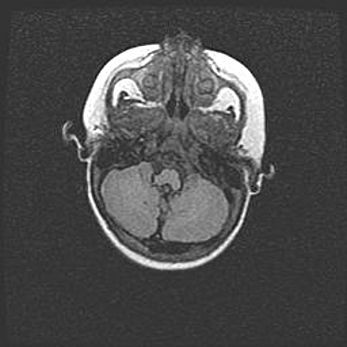

Подострая гематома правой гемисферы мозжечка.

Наружная гидроцефалия.

Возраст: 15 дней

Вес: 3100 г

Пол: женский

Окружность головы: 37 см

Срок гестации: 35-36 недель

При открытой наружной форме гидроцефалии у новорожденных расширяются и переполняются субарахноидные пространства.

Кровоизлияния в мозжечок имеют две клинико-анатомические формы: полушарные гематомы и кровоизлияния в червь.

К появлению этой патологии может привести: повреждения головного мозга, возникающие в результате асфиксии и гипоксии плода при беременности, или травмы во время родов. Редко гематома мозжечка может быть результатом первичной коагулопатии и сосудистой мальформации, диссеминированном внутрисосудистом свертывании, изоиммунной тромбоцитопении.